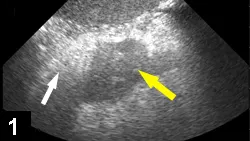

Figure 1. Ultrasound of the right upper quadrant of a dog’s abdomen showing changes often noted with pancreatitis (eg, thickened, hypoechoic pancreas [yellow arrow], surrounding hyperechoic mesentery [white arrow]).

• Ultrasonography (See Figure 1) remains one of the most common methods to diagnose pancreatitis.

• A skilled ultrasonographer can often identify characteristic ultrasonographic changes consistent with pancreatitis (eg, enlarged hypoechoic or mixed echogenic pancreas with surrounding hyperechoic mesenteric tissue, variable distention/functional obstruction of the biliary system, small amounts of free fluid in the abdomen consistent with focal peritonitis, thickened or corrugated appearance to the duodenum, intestinal ileus).

• A normal ultrasound does not rule out pancreatitis.